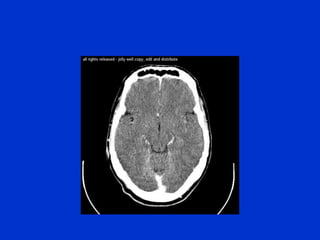

The document provides an overview of normal brain anatomy including key structures like the central sulcus, lateral sulcus, white matter tracts, brain stem, ventricular system, and basal cisterns. It was authored by Dr. Maliha Fansur, Assistant Professor at SIMS/SHL, who appears to have expertise in neuroanatomy.